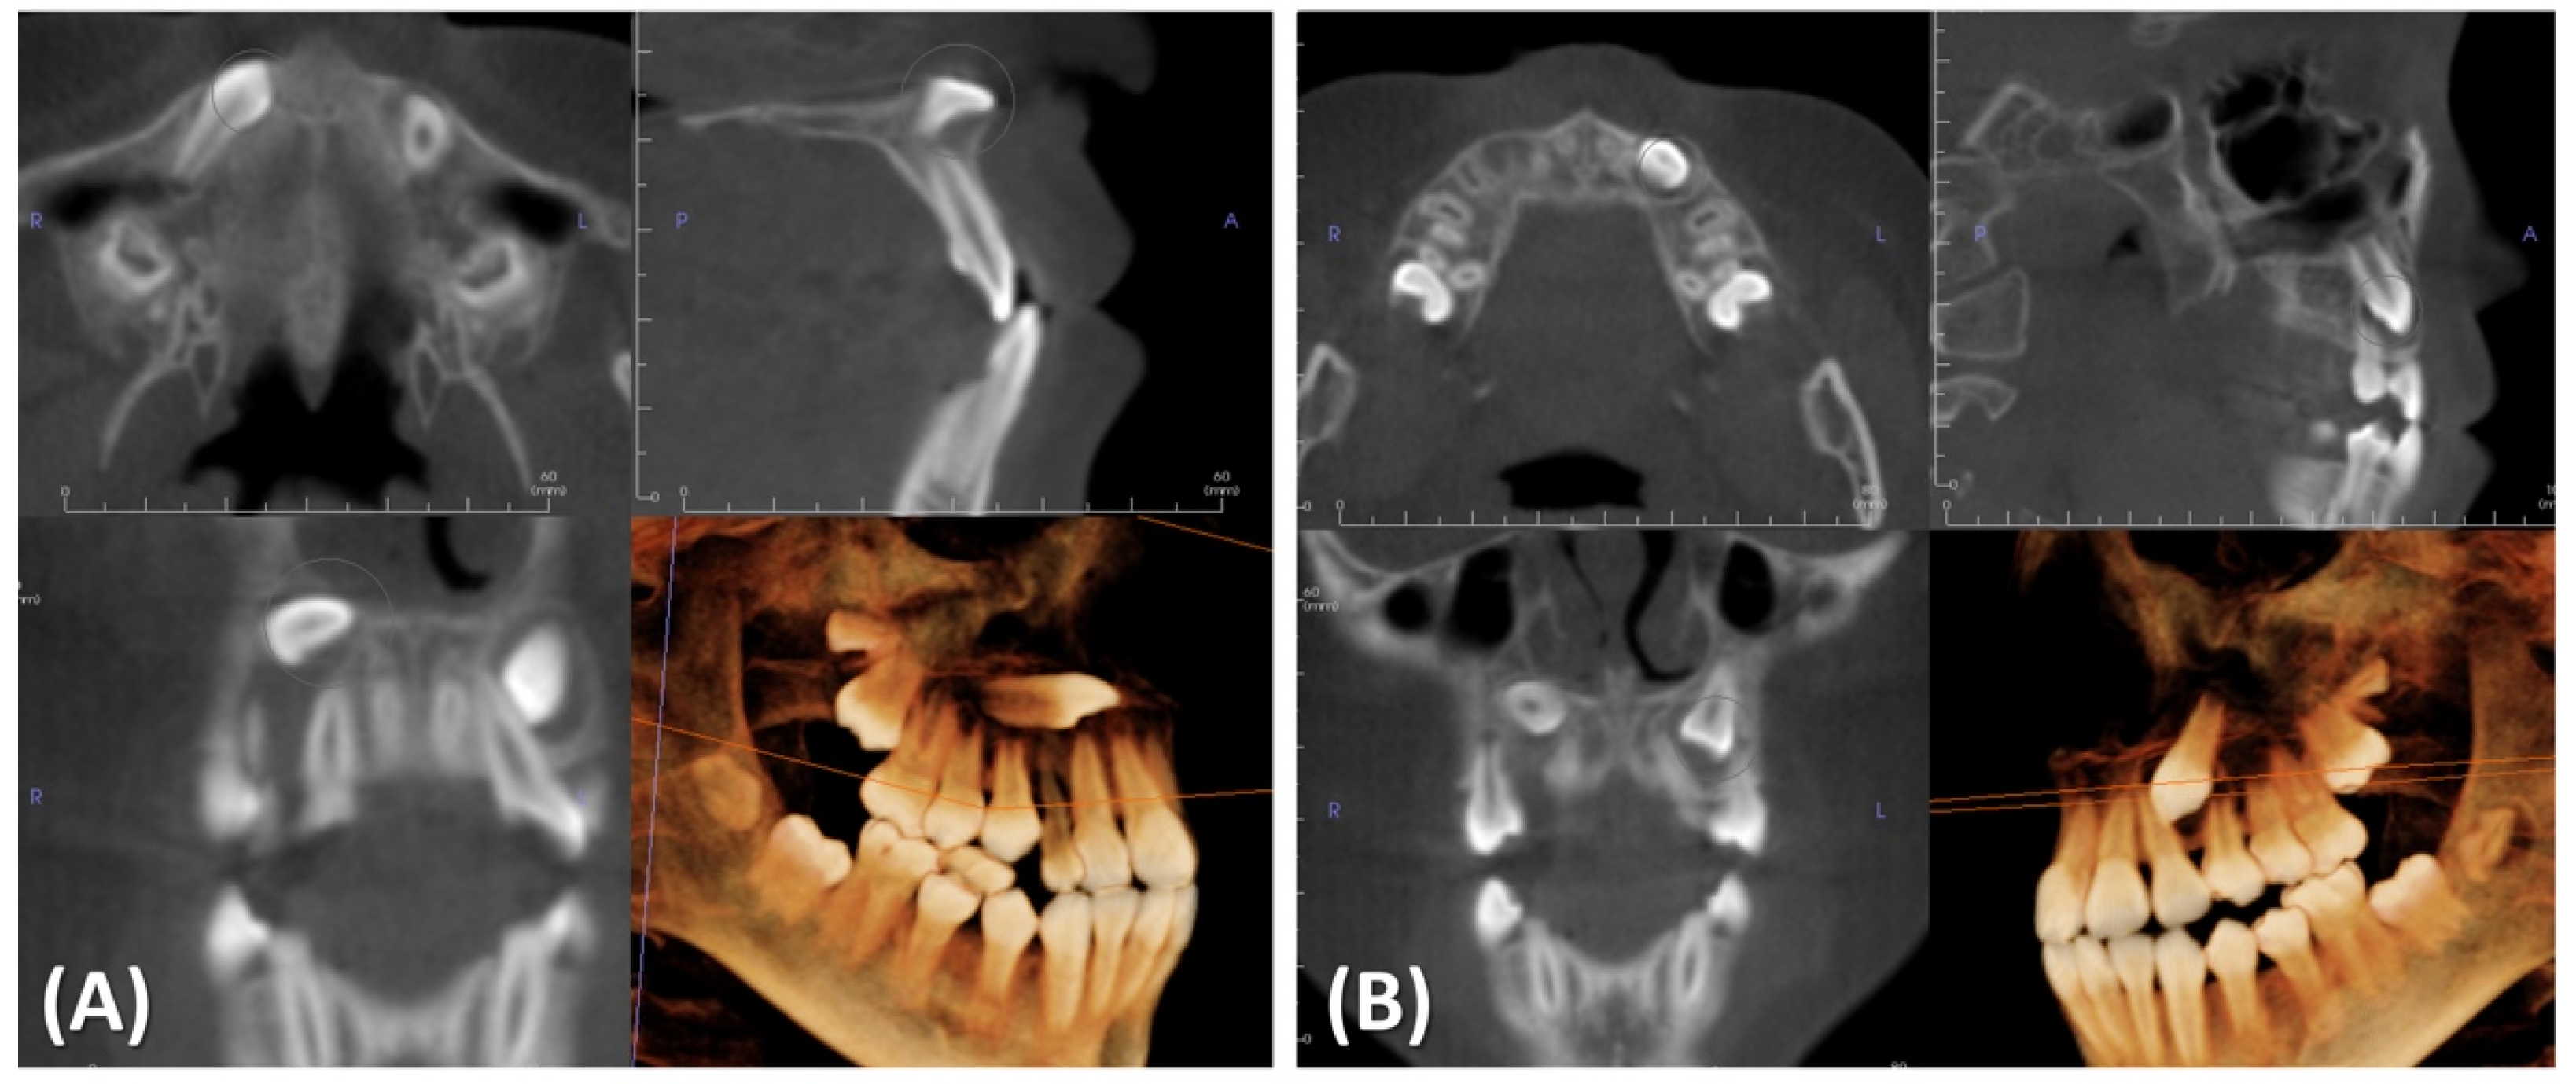

2.4. Treatment Progress